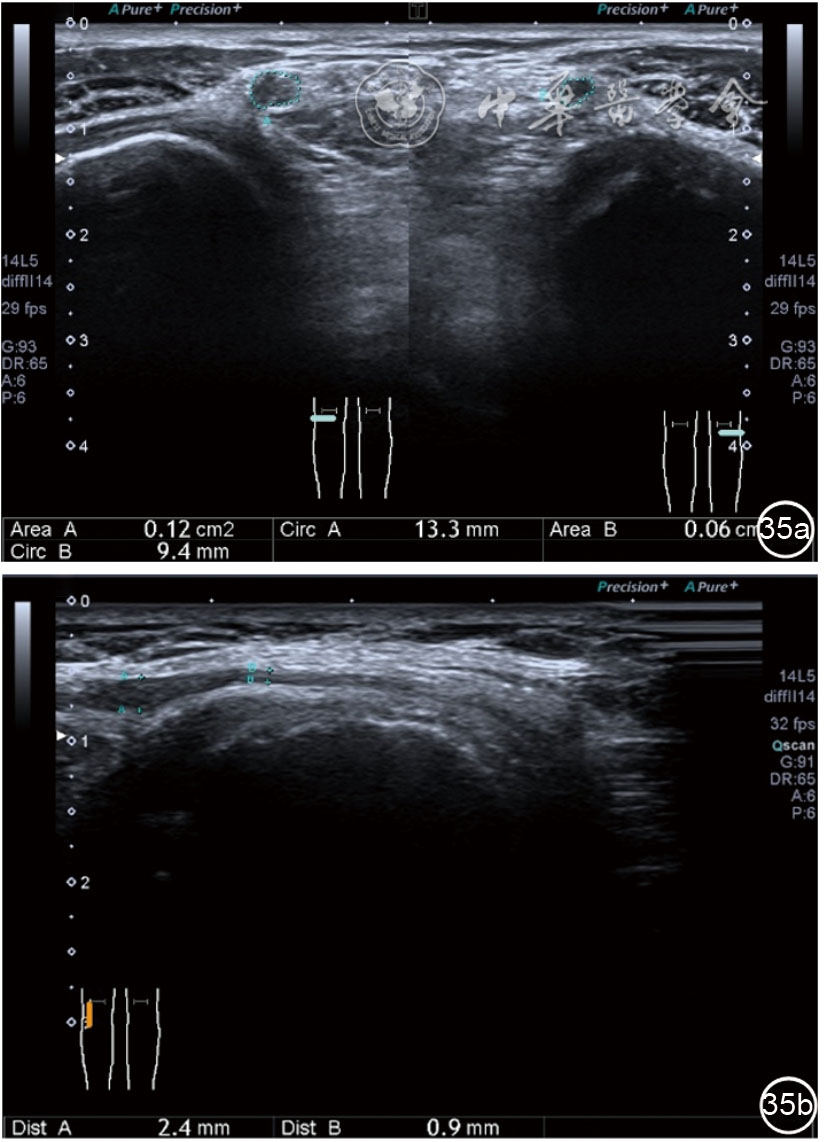

患者采取侧卧位,患肢在上,屈膝20°。应用10~18 MHz高频线阵探头,扫查深度1~3 mm。长轴和短轴结合双侧对比扫查。超声影像学所见:短轴可见卡压腓总神经近端增粗,面积增大;长轴可见腓总神经卡压处变细,其近侧肿胀、回声减低,而在卡压远侧则表现正常(图35);一些受压严重者可以出现神经周围积液,卡压神经部位的筋膜增厚(图36);受压神经内血流增加对临床诊断意义更大(图37);探头在病变神经处加压常可引起神经刺激症状。腓总神经支配的肌肉有失神经支配改变,表现为肌肉回声增高和肌肉萎缩(图38)。

图35 超声短轴可见卡压腓总神经近端增粗,面积增大;长轴可见腓总神经卡压处变细,其近侧肿胀、回声减低

图36 超声图像示腓总神经周围积液,卡压神经部位的筋膜增厚